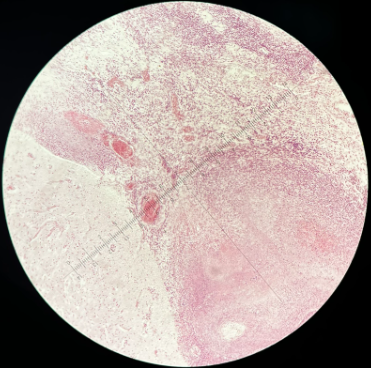

Kopsude krooniline alveolaarne emfüseem